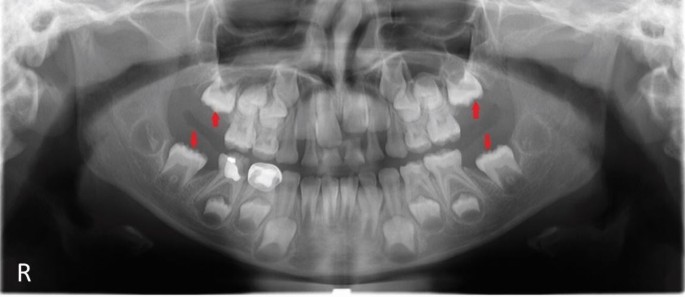

An eight-year-old girl (precise age: eight years zero months) presented with clinical absence of all four FPMs (16, 26, 36, 46). Medical and family histories were unremarkable, with no prior extractions. Panoramic radiography (Fig. 1) revealed delayed FPM development with atypical distal positioning relative to primary second molars. Using Nolla's classification, the marked teeth showed root development at stage 7, similar to premolars, while distal crypts were at stages 3 (right mandible), 2 (left mandible), and 0 (maxilla), initially suggesting second or third molars.2 However, this pattern was inconsistent with normal eruption.